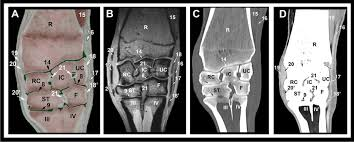

basic surface anatomy of a bone as shown on a diagram and/or normal X-ray, CT and MRI:

on a diagram

x-ray

on ct

mri